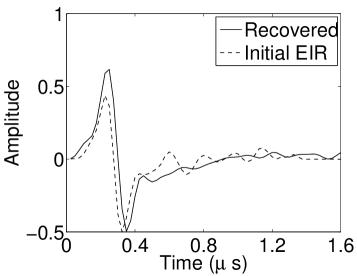

The reconstruction region ( mm2) was represented by pixels with pixel size mm in each dimension. The initial guess of the EIR employed in the VP algorithm was different than the EIR that was assumed when generating the simulated data. This served to simulate a situation in which an experimentally measured EIR contained errors.

Each element in a real-world transducer array possesses its own EIR. In practice, the differences between the EIRs are sometimes neglected and an EIR corresponding to a single element may be used to represent all elements in the array. In some of the studies below, the EIR employed to initialize the VP algorithm (EIR-2 in Figure 1(b)) and the EIR employed to produce the simulated measurements (EIR-1 in Figure 1(b)) were experimentally measured from two different transducer elements in a circular transducer array (see Sec. VI-B). EIR-1 was measured by temporally integrating the PA signal produced by a point source positioned at the focus of the transducer. EIR-2 was measured by use of the method reported in [RNR2011]. In order to investigate the sensitivity of the VP algorithm to the initialization of the EIR, we employed different EIRs obtained by degrading EIR-1 as described later. When solving the sub-problem in Line-2 of Algorithm 1, was initialized as the zero vector. Algorithm 1 was terminated after 500 iterations, since it was observed that the changes in the reconstructed images with more iterations were negligible. When implemented by use of a single core of an Intel Xeon E5-2640 CPU, each iteration required approximately 7s to complete.

As shown in Figure 6, when the error in the EIR was small (e.g., as with the EIR in Figure 6(a)), images were reconstructed with high accuracy using the VP algorithm. When the perturbations in the EIR were stronger (e.g, as in Figure 6(c)), artifacts and distortions in the reconstructed images were still significantly reduced by use of the VP algorithm; however, larger values of the regularization parameters had to be applied. When as in the initial EIR in Figure 6(e), no improvement was observed in the image reconstructed by use of the VP algorithm.

Figure 7(a) reveals that use of the inaccurate EIR in the conventional iterative method created strong artifacts and distortions. Figures 7(b) confirms that the artifacts and distortions were significantly mitigated when the VP method was employed. Image profiles for both cases are shown in Figures 7(c). The overall accuracy of the recovered EIR, shown in Figure 7(d) and 7(e), was improved, but it contained spurious oscillations.